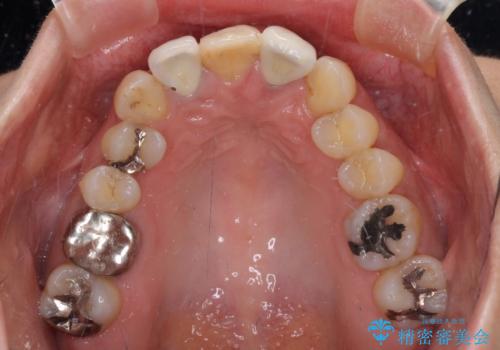

他にも奥歯の咬み合わせに問題があったので、全顎的な矯正治療を行い、前歯以外にも口を開けたときに目立つ奥の銀歯をセラミッククラウンにて補綴治療を行うこととしました。

前歯の横幅が大きいことも気になっていたので、矯正治療で前歯5本の幅をコントロールしながら移動させ、治療開始前より一回りサイズの小さいセラミッククラウンを装着することができました。